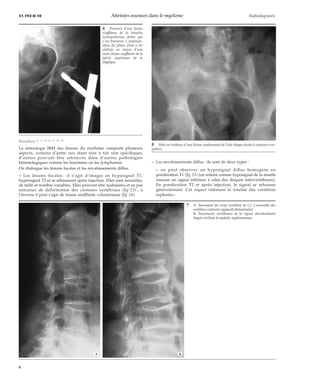

5 Myélomatose décalcifiante deWeissenbach et Lièvre avec déminéralisation osseuse diffuse (A, B, C).

Les séquences en inversion récupération (STIR) qui permettent

d’annuler sélectivement le signal de la graisse sont de très

bonnes séquences de dépistage, mais ne présentent aucune

spécificité.

Les séquences en spin-écho T1 après injection ne permettent pas

d’augmenter de façon notable la sensibilité de l’examen mais elles

semblent avoir un intérêt pour le suivi sous traitement.

D’autres séquences utilisant le déplacement chimique (Dixon,

Chopper...) accentuent le contraste moelle normale/moelle

pathologique. L’injection de gadolinium majore encore ce contraste.

Au total, le bilan minimal doit comporter des séquences T1 et T2

dans le plan sagittal au niveau rachidien ainsi qu’au niveau du

bassin et de l’extrémité supérieure des deux fémurs dans le plan

frontal.